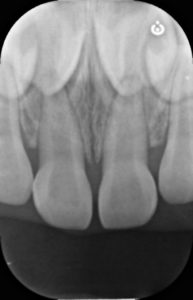

受傷直後

年齢:3歳女の子

30分前にこけて上の前歯を強打し、この写真からはわかりませんが、上の前歯の位置異常(脱臼)が生じています。

参考症例 外傷により右上前歯の脱臼が生じています